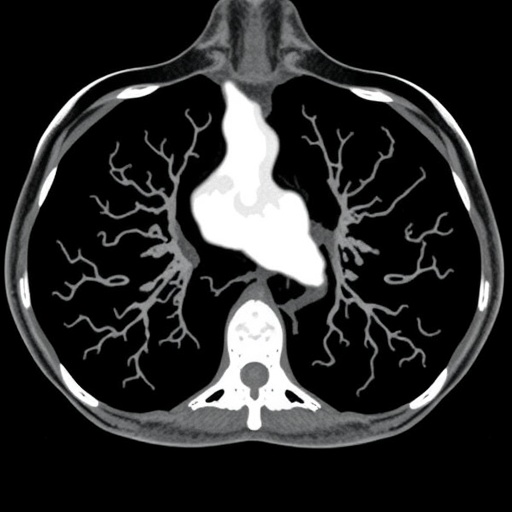

Enter 18F-fluorodeoxyglucose (FDG) PET-CT, an imaging modality that marries metabolic and anatomic information by highlighting regions of increased glucose metabolism typical of malignant cells. This hybrid imaging offers heightened sensitivity in identifying metastatic deposits, potentially uncovering occult disease that could alter staging from non-metastatic to Stage 4, thereby shifting therapeutic intent from curative to palliative. The implications for patients hinge on achieving the most accurate staging upfront, ensuring that treatment modalities align with the disease’s true extent.

Past research in locally advanced breast cancer has demonstrated that 18F-FDG PET-CT can outperform traditional imaging in upstaging patients, thus supporting its integration into routine practice. However, the spectrum of breast cancer subtypes exhibits significant variation in FDG avidity. Invasive ductal carcinoma (IDC), the most prevalent subtype, generally exhibits higher glycolytic activity, rendering PET-CT a reliable tool. Contrastingly, invasive lobular breast carcinoma (ILBC), characterized by its indolent growth pattern and distinctive histopathology, often demonstrates lower FDG uptake, raising concerns about false negatives and underestimation of disease burden.

Early indications from this study suggest that while ILBC’s lower FDG-avidity poses challenges, advanced PET-CT imaging techniques may still unveil critical metastatic sites previously undetected by conventional imaging. This nuance underscores the technological advances in PET-CT hardware and software, including time-of-flight detection, improved spatial resolution, and refined attenuation correction algorithms, which collectively enhance lesion conspicuity even in metabolically less active tumors. These innovations breathe new life into PET-CT’s diagnostic promise, extending its relevance beyond traditional cancer phenotypes.